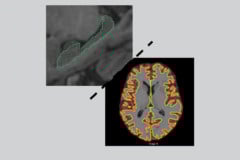

Clinical relevance of brain atrophy subtypes categorization in memory clinics

Catégorie(s) : Commented publications, For all